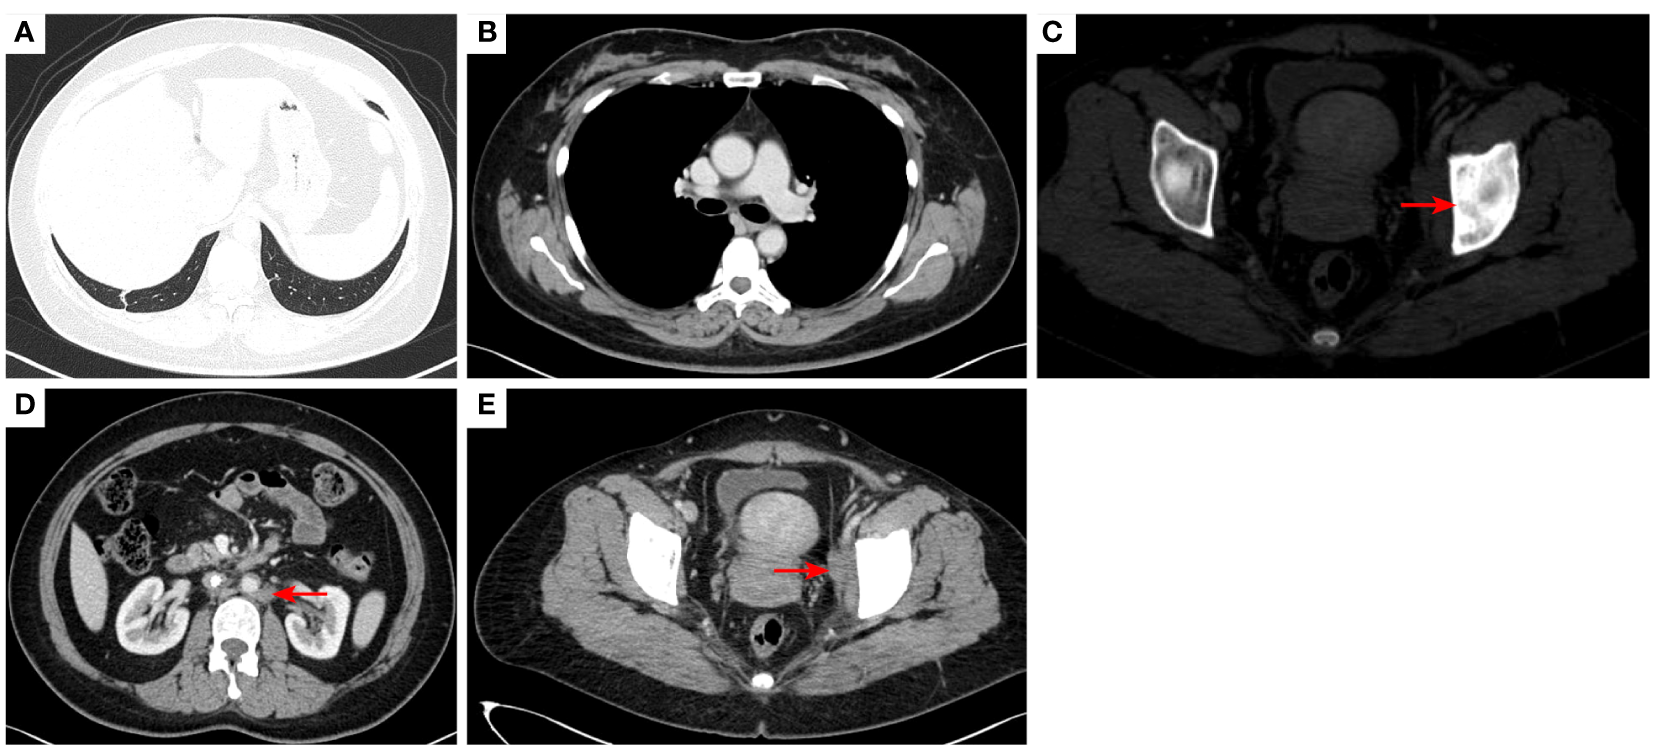

Figure 10

2023–4-13: The original right lower lobe of lung metastatic tumor disappeared (A); The original right hilar enlargement lymph node disappeared (B); Left acetabular metastases [red arrow, (C)]. The short diameter of retroperitoneal lymph nodes was 0.89cm [red arrow, (D)], and the short diameter of left pelvic lymph nodes was 2.13cm [red arrow, (E)].The efficacy was PR. PR, Partial response; SD, Stable disease; PD, Progressive disease; irRECIST, immune-related response evaluation criteria in solid tumors.